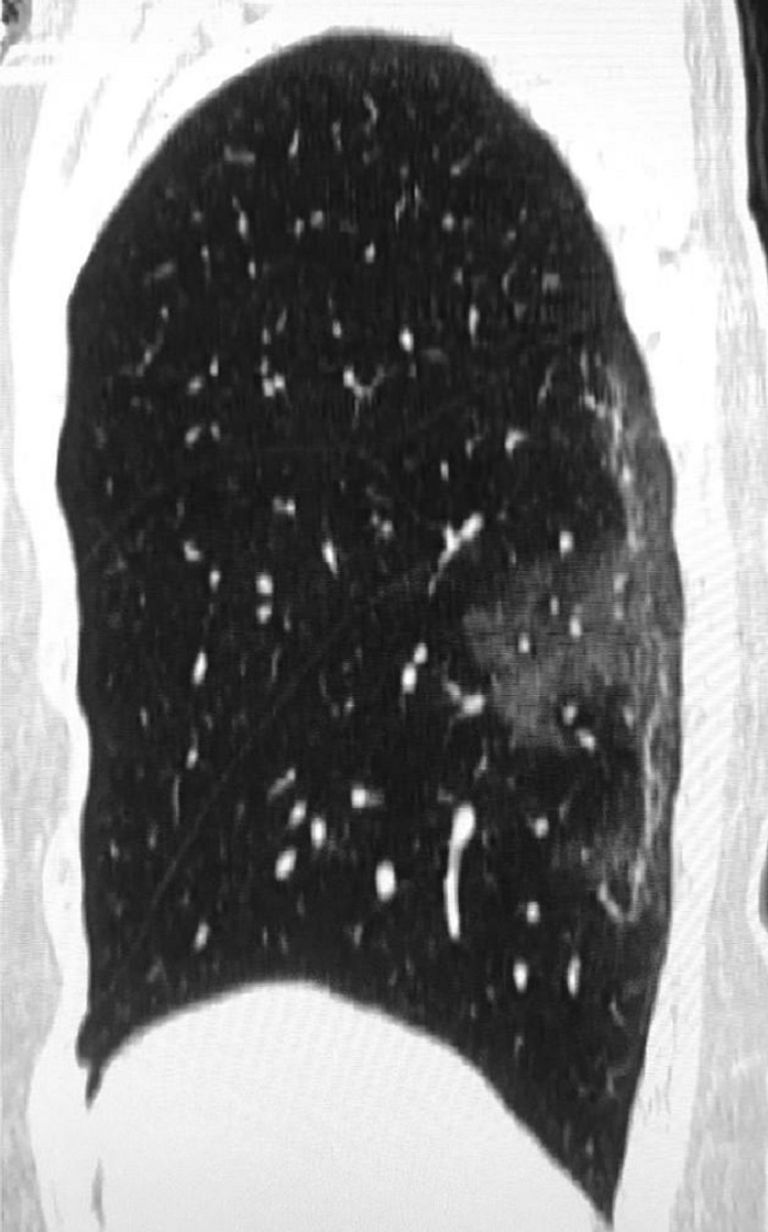

ويظهر من الأشعة وجود بقع بيضاء في المناطق السفلى من الرئتين، والتي تشير إلى ما يسميه أطباء الأشعة منظر "الزجاج المغشى"، وهو الامتلاء الجزئي للحويصلات الهوائية، بحسب صحيفة "ديلي ميل" البريطانية.

كما بينت الأشعة المقطعية لسيدة عمرها 54 عاماً، أصيبت بفيروس كورونا بعد سفرها إلى مدينة ووهان الصينية، نفس الامتلاء الجزئي للحويصلات.

وظهر في الأشعة الخاصة بسيدة من مقاطعة سيتشوان الصينية، تبلغ من العمر 45 عاماً، جاءت نتائج فحوصها إيجابية للإصابة بـ"كوفيد-19"، بعد عودتها من اليابان، بقع بيضاء بالفص العلوي الأيسر للرئة.